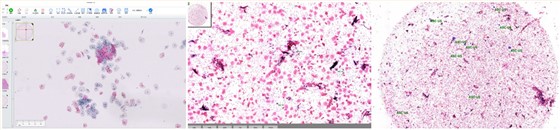

AI判读:

基于AI的超分辨成像+智能判读

高特异性、敏感性:

针对乳腺癌、宫颈癌、结直肠癌、白血病开发独立的人工智能诊断模块,单视野的敏感性和特异性都超过97%,整张玻片的敏感性低度病变及高度病变类型病例的检出率超过96%